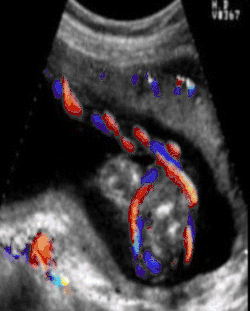

Doppler ultrasound showing a nuchal cord

A study published in 2004 was done to establish the sensitivity of ultrasound in the diagnosis of a nuchal cord. Each of 289 women, induced the same day, underwent a transabdominal ultrasound scan with an Aloka 1700 ultrasound machine with a 3.5 MHz abdominal probe, using gray-scale and color Doppler imaging immediately prior to induction of labor. Presence of the cord was sought in the transverse and sagittal plane of the neck. A nuchal cord was diagnosed if the cord was visualized lying around at least 3 of the 4 sides of the neck. A cord was actually present at delivery in 52 of the 289 women. Only 18 of the 52 cords or 35% of the nuchal cords were detected on ultrasound done immediately before delivery, and 65% of nuchal cords were not detected. Of the 237 cases where there was no cord at delivery, ultrasound had false positive results, i.e. diagnosed a cord in 44 of the 237 cases (19%) in which there was no cord present at all. In this study, ultrasound was only 35% accurate at finding a single loop, and only 60% accurate at detecting a nuchal cord wrapped multiple times around the neck.[9]